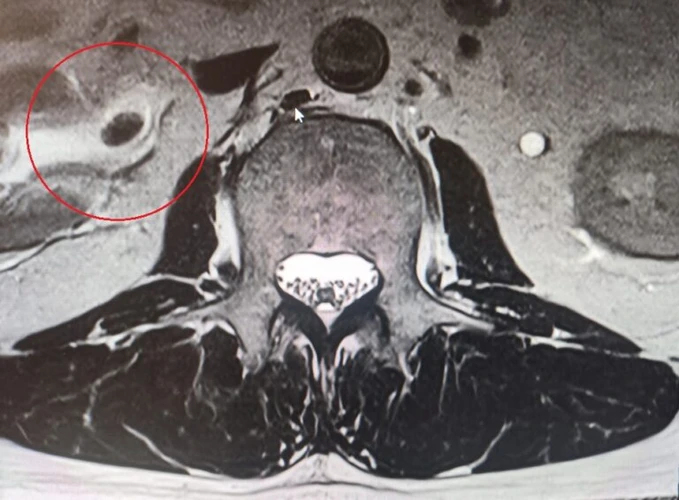

Resim 1. Loner MRG'de aksiyal kesitte sağ börekte hipointens lezyon görülmekte.

Çekilen bel MR’ında sağ böbrek pelvisinde üreter girişinde 1.5 cm çapında böbrek taşı tespit edildi.